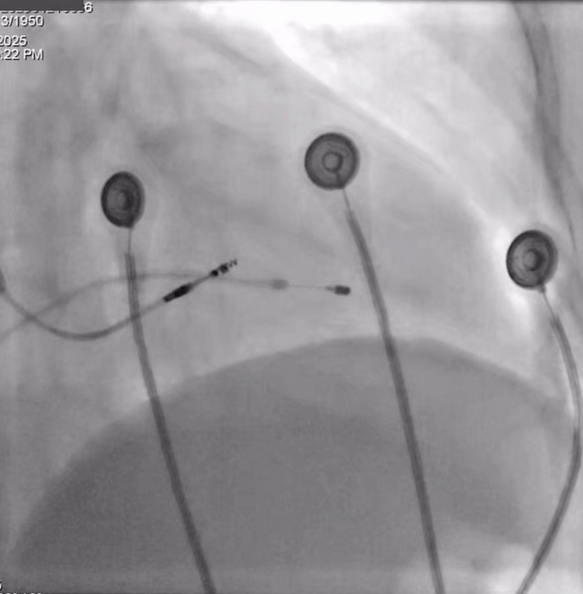

术中影像下最后确认植入位点

图5

术后即刻参数QRS:99ms,达峰时间:74ms,SV:21ms。